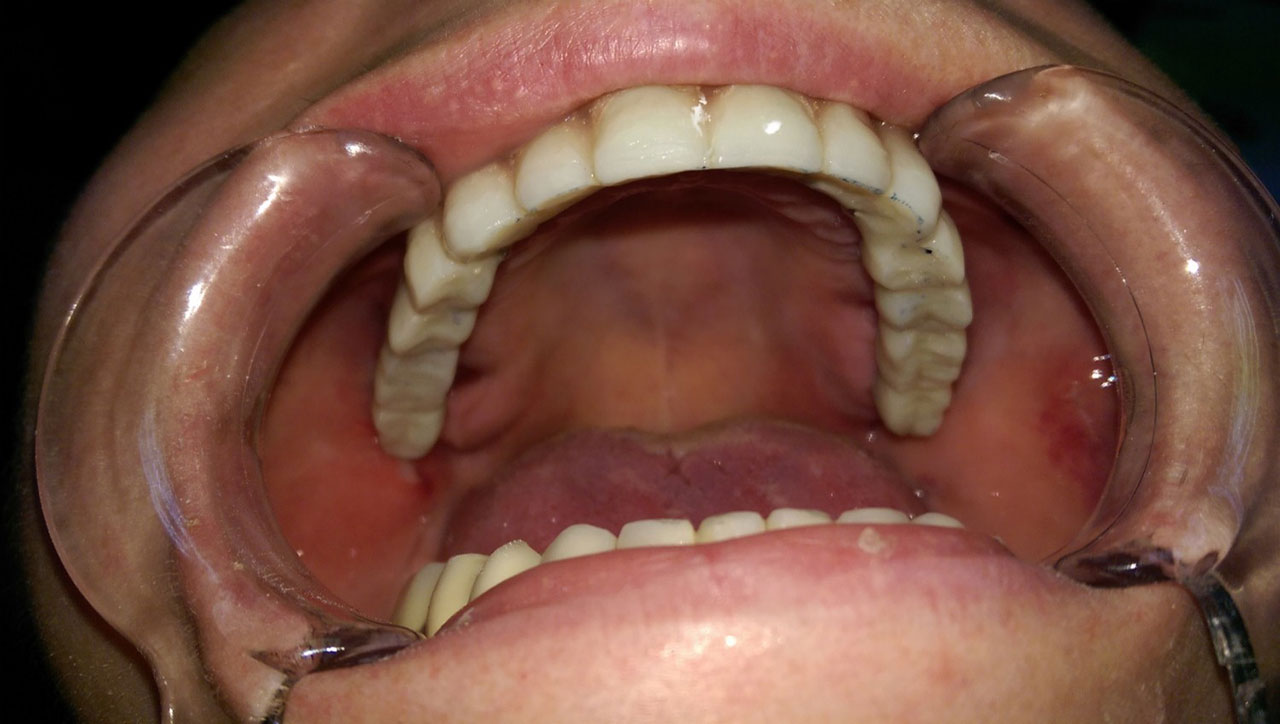

Műtét másnapján, implantátumok a szájban.

• esettanulmany-09

Szájban a hosszútávú ideiglenes híd.(Fém vázzal erősített műanyag híd.)

• esettanulmany-12

Így néz ki szájban a hosszútávú ideiglenes híd.(Fém vázzal erősített műanyag híd.)

• esettanulmany-44